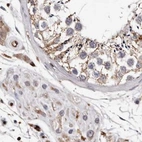

Immunohistochemistry analysis in human lymph node and cerebral cortex tissues using Anti-GIMAP4 antibody. Corresponding GIMAP4 RNA-seq data are presented for the same tissues.